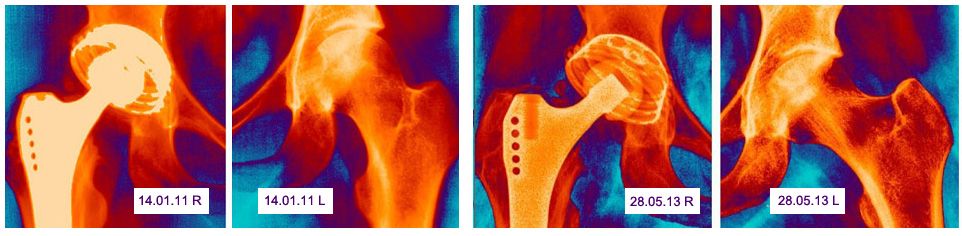

Специализированный центр по лечению асептического некроза